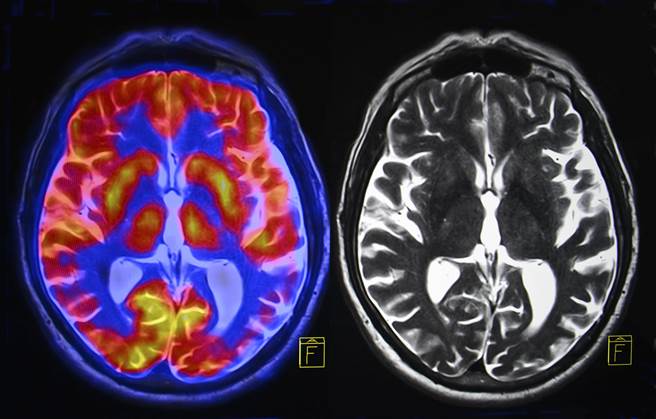

英国广播公司新闻网(BBC News)报导,科学家为一名患有癫痫的87岁患者测量脑电波时,患者心臟病发作,危及性命,因此意外让科学家有了垂死大脑的纪录。

结果显示,在心臟停止搏动的前后30秒,这名男性病患的脑电波模式与做梦或回忆相同。

齐默现为美国路易维尔大学(University of Louisville)神经外科医师。他说,在患者心臟停止向大脑供血前的30秒,脑电波模式与人执行需要高认知的任务时相同,像是集中注意力、做梦或回忆过去。

患者的脑波会在心臟停止搏动后持续30秒。齐默说:「这可能是我们人生经歷的最后一次回顾,在死前最后几秒透过大脑重演。」